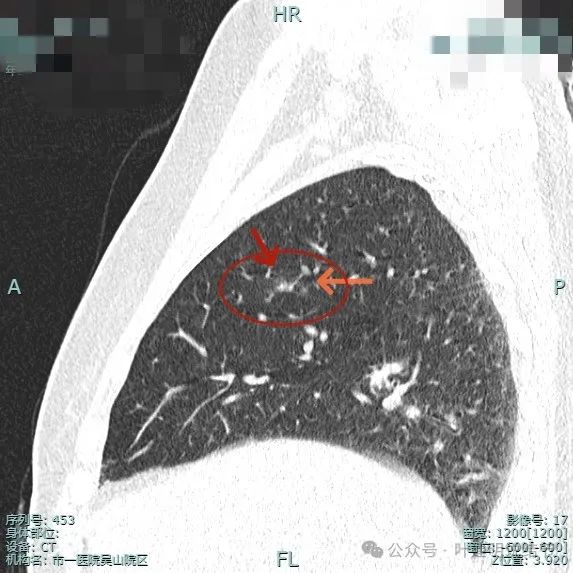

混合密度,叶间裂牵拉影响,灶内密度杂乱感。

灶内有小空泡征,表面浅分叶,灶内实性成分明显,有微血管进入病灶。

叶间裂牵拉向病灶侧,此视角看瘤肺边界较为清楚。